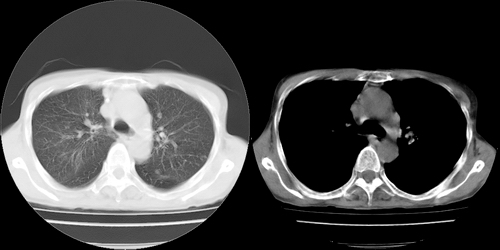

以下是引用lihuuuu在2006-7-18 18:16:00的发言:[br]支持肺结核诊断[br]本病例符合结核“三多”“三少”特征(多病灶、多形态、多钙化、少肿块、少堆积、少增强)中的前五个特征,另外左下叶背段有不张样改变-考虑伴有支气管内膜结核所致段不张。

以下是引用yang4132在2006-7-18 10:04:00的发言:[br]两肺多发 多形态病变,部分半纤维条索和斑点壮钙化,胸膜肥厚粘连,考虑结核。